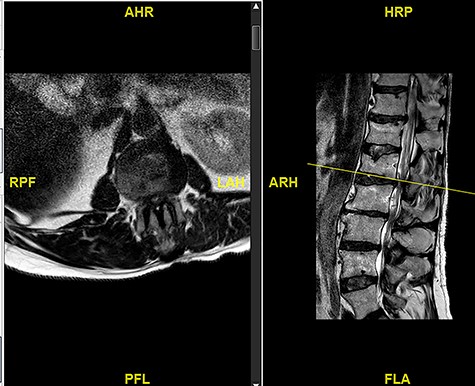

A 56-year-old male patient lumber decompression in a local neurosurgical centre for severe canal stenosis at L1/2 and L2/3 (Fig. 1) level after presenting with bilateral leg weakness and perianal numbness. Three months later he presented with recurrence of right leg pain radiating into the calf and worsening back pain as well as distal lower limbs weakness bilaterally with no sphincter problem. Following an magnetic resonance induction (MRI), which revealed a disc prolapse at L1/2 (Fig. 2), the patient was referred to our Centre. The images were reviewed by a consultant radiologist and as a possibly of intradural herniated disc disease was described. Intraoperatively no extradural disc prolapse was found, so midline durotomy was performed. Intradural disc herniation (IDH) was identified, which was communicating with the disc space through a midline defect in anterior dura (Fig. 3). This was removed extracted under the microscope. Post-operatively, he had a CSF leak needing re-suturing of dura. The patient did make a good post-operative recovery with no major sensory or motor deficits or sphincter disturbance.

Intraoperative picture showing durotomy and intradural disc being delivered at L1/2.